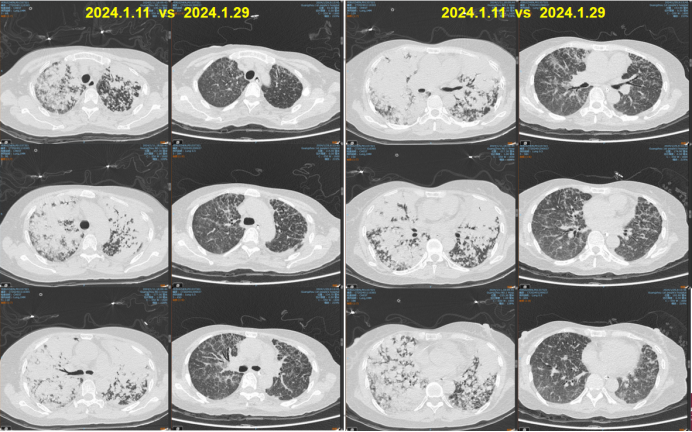

病例5:63岁女性患者,因呼吸困难20天、加重1天入院患者20天前无明显诱因出现活动性气促,伴心悸、咳嗽、咳白痰;1天前患者呼吸困难症状加重,稍行走5米后即气促严重;指脉氧饱和度72%,氧合指数64.2 mmHg(HFNC:流量55 L/min,吸氧浓度95%),查肿瘤指标CEA>1000 ng/ml予气管插管机械通气。床旁纤支镜可见气管膜稍充血,未见明确新生物,分泌物少病理提示红细胞背景中见大量腺癌细胞,免疫组化符合肺腺癌。患者诊断为肺腺癌伴纵隔淋巴结、双肺内及胸腰椎多发转移。基因检测结果提示存在EGFR经典突变(19外显子缺失)。给予靶向治疗联合抗感染、营养支持及免疫调节等治疗,患者气促明显改善,胸部CT示双肺多发病灶显著吸收(图8)1周后拔管脱机,2周后出院,逐步恢复居家生活,目前仍在长期门诊随访

图片

8  患者治疗前后胸部CT对比